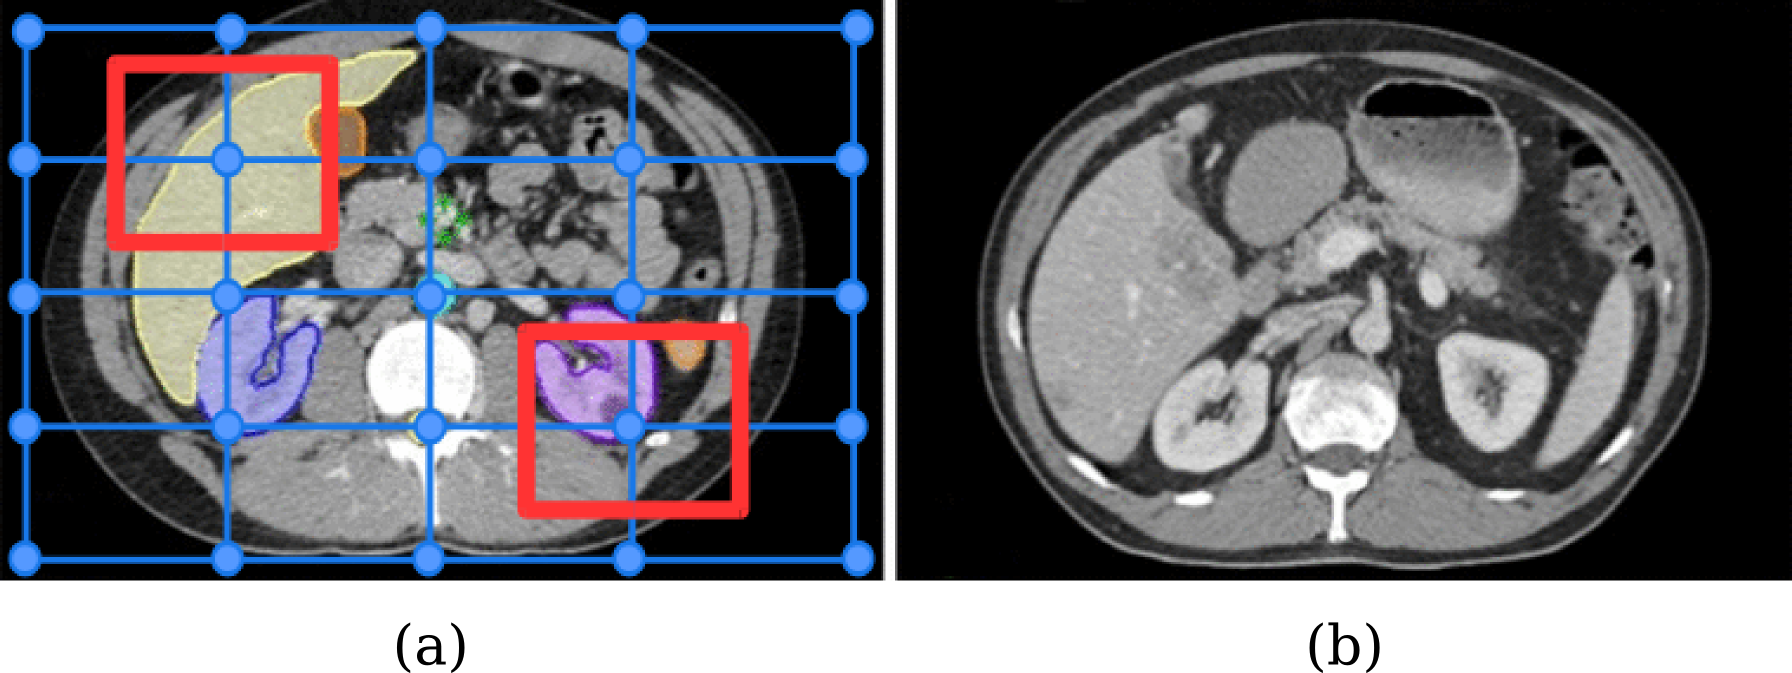

Let us assume that we are given a source 3D3𝐷3D volume (or image) I𝐼I, source 3D3𝐷3D segmentation mask SIsuperscript𝑆𝐼S^{I}, and the target 3D3𝐷3D volume (or image) J𝐽J. The size of the segmentation mask is the same as that of the corresponding image. The segmentation mask is formed by the elements (or voxels) sk𝒞subscript𝑠𝑘𝒞s_{k}\in\mathcal{C}, where 𝒞𝒞\mathcal{C} is the set of classes. Every class c𝒞𝑐𝒞c\in\mathcal{C} is associated to a different anatomical structure (organs, tissues, etc) as depicted in Figure 1. Without loss of generality, we assume that the elements in the class set 𝒞𝒞\mathcal{C} are the discrete variables starting from one.

where, f(Ω¯liSI,c)𝑓superscriptsubscript¯Ωsubscript𝑙𝑖superscript𝑆𝐼𝑐f(\bar{\Omega}_{l_{i}}^{S^{I}},c) is the number of voxels of class c𝑐c in the patch Ω¯liSIsuperscriptsubscript¯Ωsubscript𝑙𝑖superscript𝑆𝐼\bar{\Omega}_{l_{i}}^{S^{I}} (see Figure 1 for a graphical example). Notice that one can use other criteria to find the dominant class. Also note that the semantic segmentation mask SIsuperscript𝑆𝐼S^{I} for the source image is given as an input to the registration framework, and is not imputed as a latent variable.

Refer to caption

Figure 1: The multi-metric deformable registration algorithm uses a different aggregation of metrics depending on the context, which is determined by the dominant class in the corresponding source image support area. In the example, we can observe that the liver (in yellow) and the kidney (in violet) are the dominant classes for the two highlighted control points. Note that, during training, both source (a) and target (b) semantic labels are required to compute the loss function ΔΔ\Delta. However, at test time, we only require semantic labels for the source image (a) to choose the dominant class.